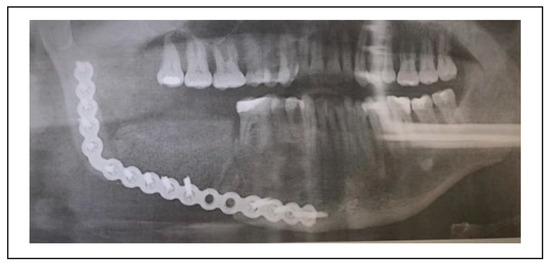

Odontogenic Keratocyst: A Clinical Entity With Favorable Response to Active Decompression and Distraction Sugosteogenesis

by Juan-Pablo Porte, Lidia M. Guerrero, Bonifacio Rivera, Andres Wiscovitch and Jaime Castro-Núñez

Craniomaxillofac. Trauma Reconstr. 2022, 15(4), 268-274; https://doi.org/10.1177/19433875211035237 - 5 Aug 2021

Cited by 2 | Viewed by 467

Objective: The purpose of this study was to determine the usefulness of active decompression and distraction sugosteogenesis (ADDS) for the management of non-syndromic odontogenic keratocysts (OKC). Materials and Methods: A retrospective case series study was designed and implemented. The study observed the Declaration [...] Read more.

Objective: The purpose of this study was to determine the usefulness of active decompression and distraction sugosteogenesis (ADDS) for the management of non-syndromic odontogenic keratocysts (OKC). Materials and Methods: A retrospective case series study was designed and implemented. The study observed the Declaration of Helsinki on medical protocol and ethics and it was approved by the university’s Institutional Review Board (IRB). The medical files of all patients who underwent ADDS for OKCs of the jaws at the Department of Oral and Maxillofacial Surgery of a tertiary university-affiliated medical center were reviewed. Data were collected on patient’s age, gender, presenting signs and symptoms, lesion location, locularity, pre-ADDS, size of the lesion, post-ADDS, pain, days with bloody discharge and/or proteinaceous fluid inside the system’s external unit, days to achieve hermetic seal, size of the lesion 2 weeks after ADDS, percentage of reduction, patient’s complaints/complications, and follow-up period. Preand post-ADDS panoramic radiographs were reviewed for reduction parameters. Results: Six patients, 5 males and 1 female, with an average age of 45.16 years (range 16–74 years) were studied. ADDS was performed during 4 weeks in all patients. During the therapy, the extraoral unit collected blood during 2.83 days in average. In average, after the third day, the cystic cavity started to drain a proteinaceous fluid for about 9.33 days (range 6–15 days). The average pre-ADDS Standard Lesional Area Index (SLAI) was 18.17 cm2 (range 4.40 cm2–34.58 m2) and, after 2 weeks of ADDS, the average SLAI was 5.47 cm2 (range 0.49 cm2–15.39 cm2). The average percentage of reduction, after 2 weeks, was 73.93% (range 55.49%–97.51%), which yielded an overall good reaction of OKCs to ADDS. No significant reduction of the lesions was observed from week 2 to week 4, when ADDS ceased. All lesions were enucleated after 3 months. After an average of 14 months of follow-up (12 to 17 months), no signs of recurrence have been observed. Full article

Show Figures

Figure 1